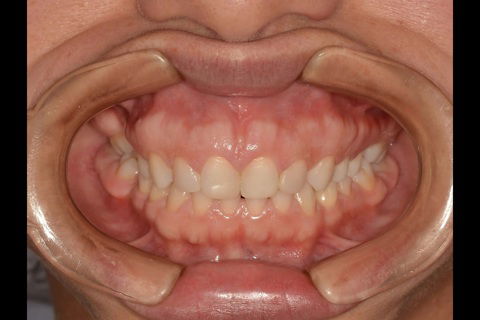

Fotos do caso